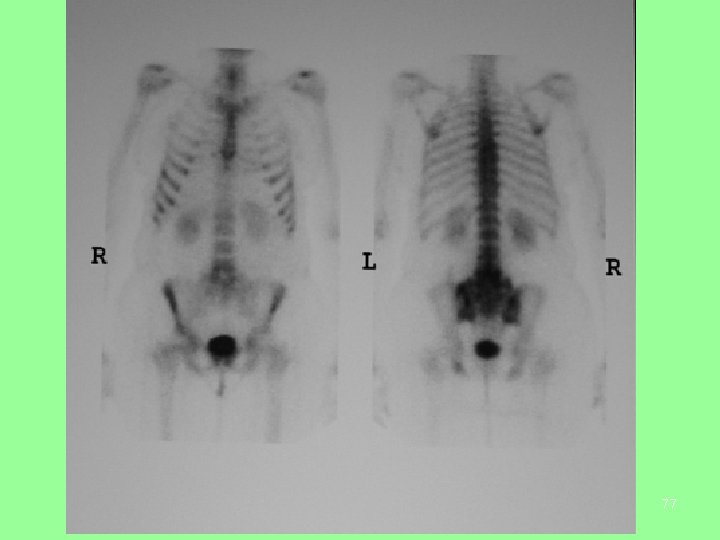

• PET Scan showing diffuse spread of prostate cancer to bone. PET has the advantage over traditional bone scanning in its ability to differentiate active from dormant disease. 59

Prostate cancer metastasized in bones 78